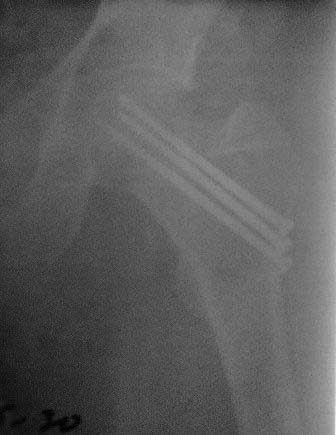

Обратился б-ной около 40 лет, три месяца назад оперирован в г.Алмате. При осмотре ходит с двумя костылями, беспокоят постоянные боли, симптом прилипшей пятки положительный, посмотрел под Р-скопией; сращения нет.

Понимаю, показано эндопротезирование, но  можно  ли органосохраняюшие операции с  аутопластикой? Остеосинтез выполнен не совсем правильно (три винта должны быть расположены субкортикально, а не в ряд, поэтому имеется плохая ротационная стабильность). Но стояние фрагментов правильное, 3 месяца для шейки не срок. Отложите вопрос о протезировании еще на 3 месяца, есть шанс срастить перелом при исключении нагрузки.  При выполнении органосохраняющих операций результат будет хуже, чем при протезировании.

P.S.   Р-снимки сразу после операции,  и вчерашные.